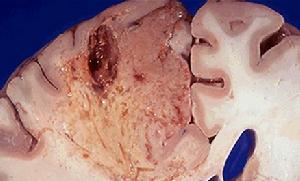

腦組織梗死液化(2)腦梗死:常起病突然,根據病情有穩定型和進展型之分,前者指病情穩定無進展,歷時24~72h又稱完全性腦卒中11%-13%患者起病隱匿無臨床症狀和體徵,僅影像學發現有缺血灶。